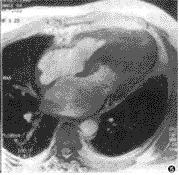

超声心动图表现:①不对称性室间隔肥厚,室间隔厚度与左室后壁厚度之比大于1.3∶1,此征过去比较重视,但现在发现也可见于其他疾病如高血压、主动脉瓣狭窄等。用二维法测左室增厚的程度更为有用。②二尖瓣前叶在收缩期前移。③左心室腔缩小,流出道狭窄。④左心室舒张功能障碍,包括顺应性减低,快速充盈时间延长,等容舒张时间延长。运用多普勒法可以了解杂音的起源和计算梗阻前后的压力差。

有心室流出道梗阻的患者因具有特征性临床表现,诊断并不困难。超声心动图检查是极为重要的无创性诊断方法,无论对梗阻性与非梗阻性的患者都有帮助,室间隔厚度≥18mm并有二尖瓣收缩期前移,足以区分梗阻性与非梗阻性病例。心导管检查显示左心室流出道压力差可以确立诊断。心室造影对诊断也有价值。临床上在胸骨下段左缘有收缩期杂音应考虑本病,用生理动作或药物作用影响血流动力学而观察杂音改变有助于诊断。此外,还须作以下鉴别诊断。